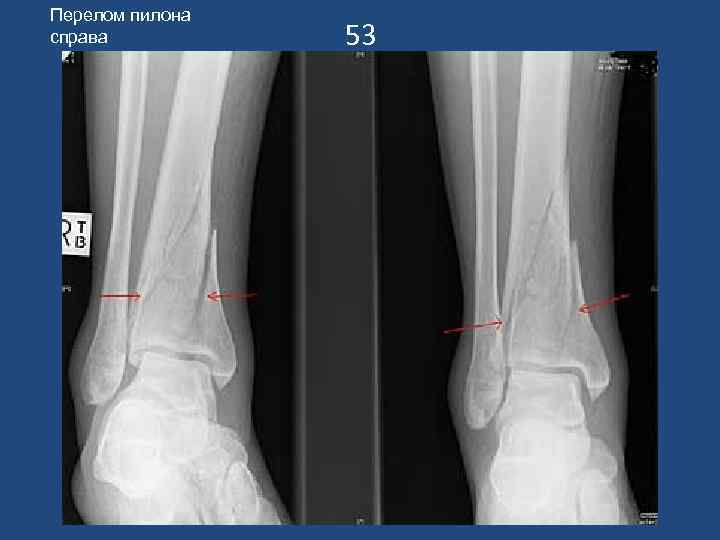

Перелом пилона справа 53